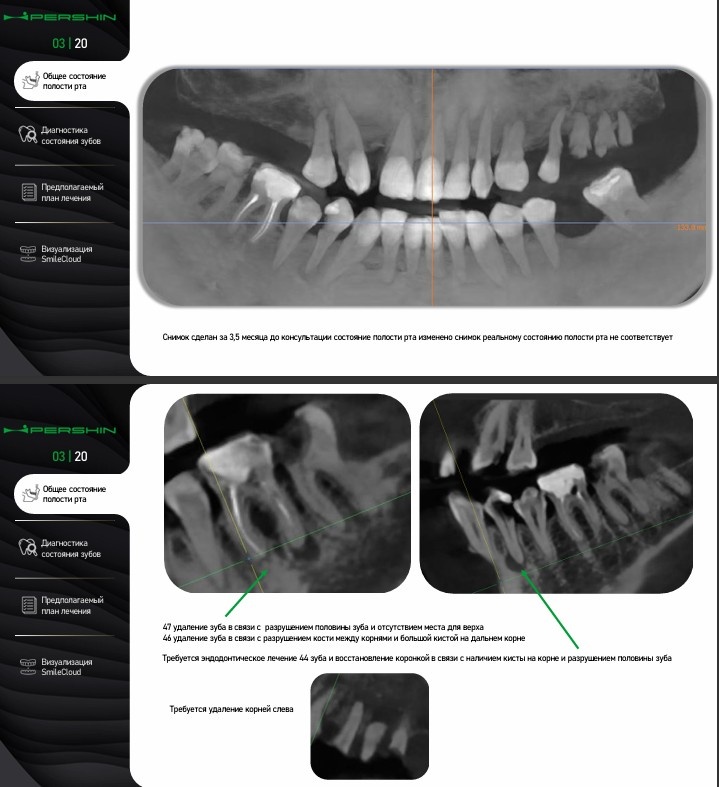

— рентген и 3D-диагностика